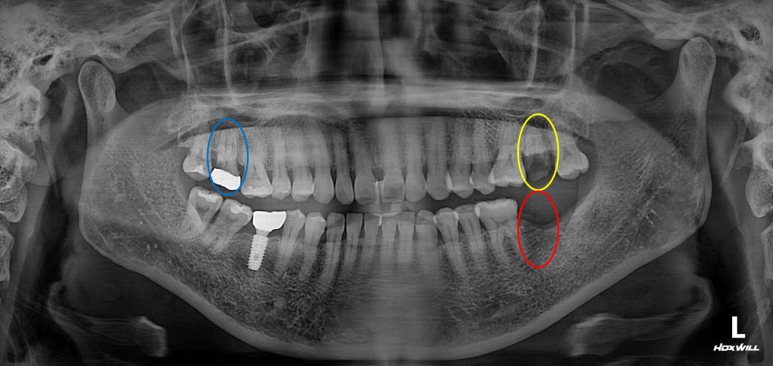

딱 봐도 치아가 조금 없는 것 같으시죠?

빨간색 동그라미로 표시된 곳에 치아가 없어요! 왼쪽 아래 두번째 어금니를 뽑으신 지 몇 년 지나신 상태였습니다.

노란색 동그라미로 표시된 치아는 뿌리만 있는 잔존치근 상태로, 살릴 수 없는 치아였어요.

그리고 마지막으로 파란색 동그라미로 표시된 치아는 기존 크라운 아래로 이차충치가 생겨서 신경치료가 필요한 상태!

주변 뼈 높이에 잘 맞게 임플란트가 심겨있어야 합니다. 너무 깊어도 얕아도 좋지 않죠. 노란색 선이 잇몸뼈 높이를 표시한 것입니다.

임플란트 고정체 (fixture) 그리고 나머지의 비율이 1:1이 넘어가지 않는게 좋습니다. 너무 얕은 땅에 긴 전봇대가 심겨있다고 생각해보시면.. 불안하죠 뭔가?

임플란트 크라운의 중간에 임플란트 고정체가 위치해 있는게 이상적입니다. 상황에 따라 달라질 순 있겠지만, 아무래도 임플란트의 뿌리가 머리의 가운데에 있는게 좋겠죠. 츄파춥스 처럼요.

결론은 어쨌든 임플란트가 아~주 이상적으로 잘 제작되었다는 뜻!